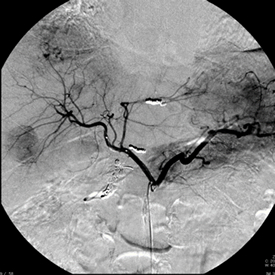

血管造影検査を用いた肝細胞癌に対する肝動脈化学塞栓療法。

カテーテルを腫瘍濃染の近くまで進めて塞栓しています。